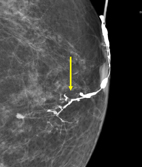

乳管攝影(ductography or galactography)對於引起乳頭分泌物的乳管內病灶具有極佳的影像解析度,這是一種侵入性的影像學檢查,首先是經由乳頭流出分泌物的乳管開口放置一支極細的乳管針(30-gauge,約0.31mm口徑)進入乳管內,然後由乳管針注射大約0.1-0.3 cc 的水溶性含碘對比劑,然後針對該乳房照X光攝影,含碘對比劑可以將正常乳管的內部情形清晰的呈現出來 (圖一),能清楚地顯示乳管是否有乳管擴張症,乳管內是否有微小的腫瘤 (圖二箭頭處),以及腫瘤的形狀、數量、位置及其距離乳頭之深度,提供正確的診斷,有助正確的治療方式。根據國外醫學研究,乳管攝影對於偵測引起乳頭分泌物的乳管病灶,其敏感度可達77-86%,準確度達80%,若是搭配3D乳房斷層攝影(digital breast tomosynthesis, DBT)的技術,此即3D斷層乳管攝影(DBT-ductography),其敏感度更高達95%,準確度高達96%。

圖二、乳管內乳突瘤